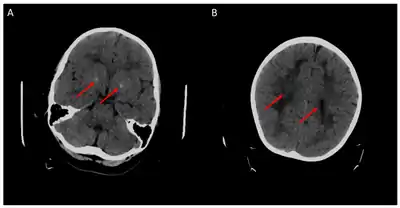

Children with the FOLR1 mutation are born healthy. Symptoms typically appear at about 5 to 24 months of age. The symptoms get worse with time. Without treatment there may be poor muscle tone, trouble with coordination, trouble talking, and seizures.[2][3] In addition, signs of psychomotor retardation, sleep disturbances, cerebellar ataxia, and delayed development of head growth can occur. At around age three, visual disturbances can develop, and sensorineural hearing loss can occur at around age six.[11] In children with cerebral folate deficiency, the cerebrospinal fluid shows low levels of 5MTHF, and a loss of white matter in the brain (leukodystrophy) may occur. As a result of the decreased levels of 5MTHF, the child experiences low levels of Vitamin B folate.[12] There is inability for the 5MTHF to be transported across the blood-brain barrier, resulting in symptoms of seizures, delayed cognitive and motor processing, and autistic features.[13]